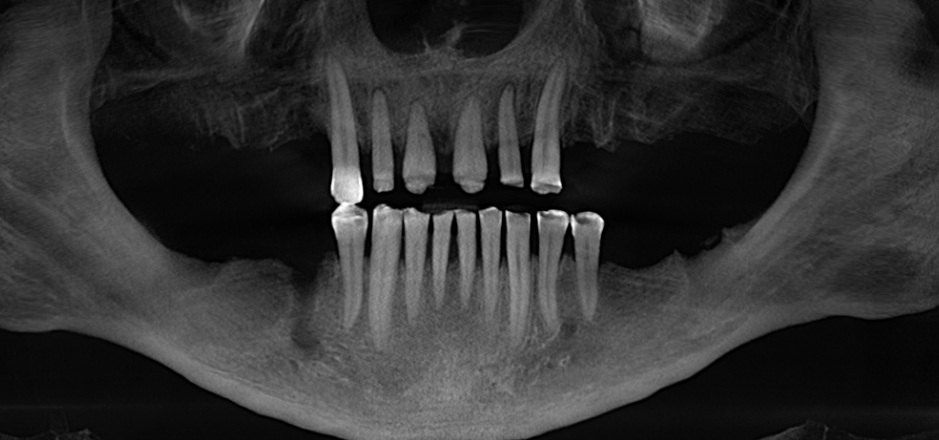

Дабы не перегружать вас обилием одинаковых картинок, я оставлю один рентгеновский снимок, но отмечу, что установка имплантатов на верхней и нижней челюсти проводилась с разницей в 10 дней.

На верхней челюсти было дополнительно удалено два боковых резца с одномоментной установкой имплантатов, так же они были установлены в области четверок и шестых зубов. Дополнительно было проведено наращивание костной ткани - двусторонний синус - лифтинг. О том, что это такое, можно почитать ТУТ и ТУТ.

Контрольный рентгеновский снимок: